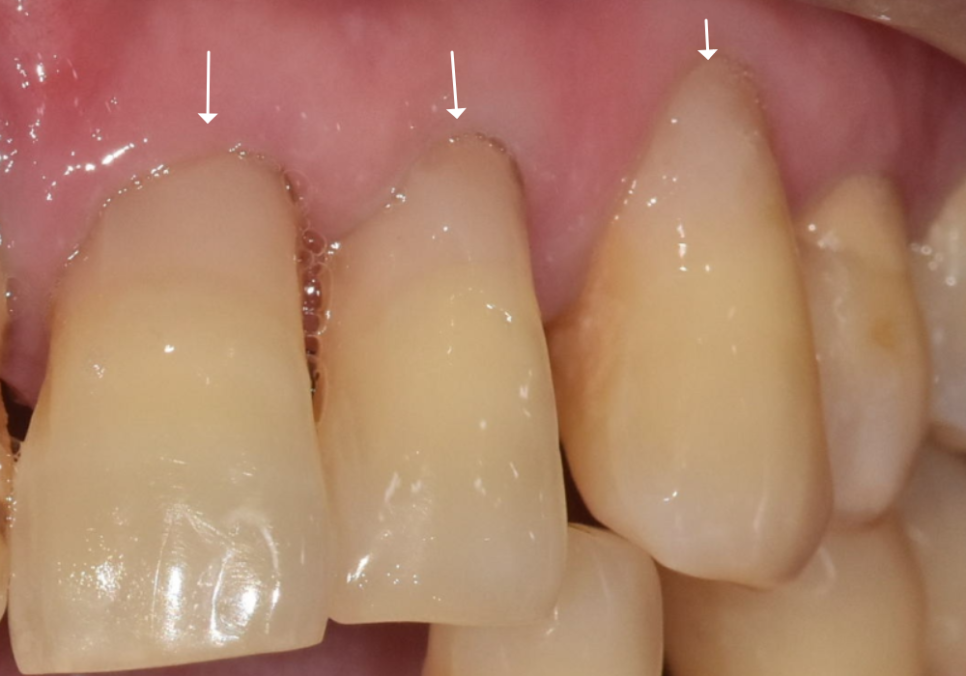

얼마 전 저희 치과를 찾으신

고령 환자분의 사례를 소개해 드릴게요.

이 환자분은 치아 뿌리 쪽이

아주 깊게 패어 있는 모습인데요.

오랜 세월 동안 마모가 서서히 진행되어,

육안으로 봐도 치아 안쪽의 신경이

드러날 정도로 심각한 상태였습니다.

보통 이 정도로 패여서 신경이 노출되면

물만 닿아도 자지러지게 아픈 게 정상이에요.

그래서 대부분은 신경치료를 하고

치아를 씌워주는 크라운 치료를 진행하게 됩니다.

이 환자분은 치아의 반 이상이

마모가 진행되었기 때문에 부러지지 않도록

지금이라도 치료를 해주는 게 중요했습니다.

환자분께서는 앞니 부위라

심미적인 부분도 중요하게 생각하셨기에

치아색에 맞는 레진으로

꼼꼼하게 메워드리는 치료를 진행했습니다.